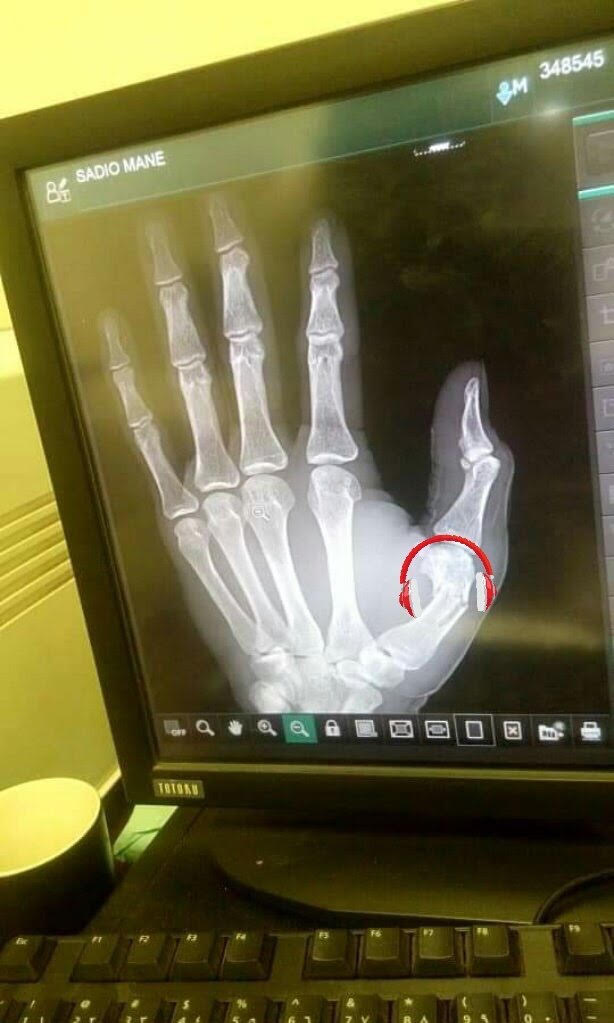

Sadio Mané s’est rendu à l’hôpital, ce lundi, pour soigner une petite blessure à la main gauche. Le pouce de l’attaquant sénégalais de Liverpool est touché. Le Sénégal doit affronter le Soudan, mardi (19h30) dans le cadre des qualifications à la CAN 2019